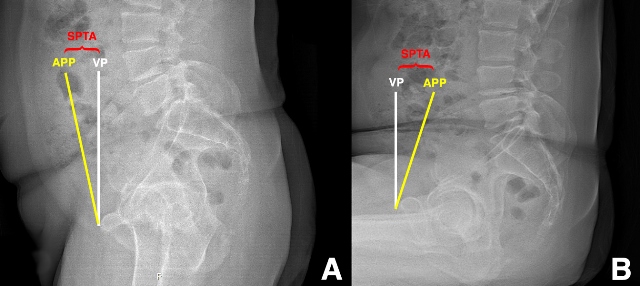

Ranawat et al. [9] explored the effects of fixed versus flexible spinopelvic relationships on the functional position of the acetabular component in a cohort of primary THA patients using frontal and lateral radiographs acquired in standing and sitting positions (Figure 1A-B). Compared to those patients with relatively flexible spinopelvic relationships, they defined those with more rigid spinopelvic motion as having less than 10 degrees of change in sagittal pelvic tilt from standing to sitting position. Of the 68 patients included for the study, over 70% had evidence of spinal pathology and 25% met the authors’ definition of having a stiff spine, or “fixed pelvis”. Flexible patients exhibited slight anterior sagittal pelvic tilt in standing to more substantial posterior tilt in sitting, the effect of which increased functional anteversion of the acetabular component by 0.75 degrees per degree of posterior tilt as they sat. Presumably, increased functional anteversion is protective against posterior dislocation during sitting. For patients with fixed spines, there was significantly less functional acetabular anteversion in the sitting position (i.e. less protection against posterior THA instability). The authors conclude that a dynamic assessment of spinopelvic motion should be part of the preoperative planning for THA. For THA patients with flexible spines, they recommend reproducing native acetabular anteversion, and they speculate that patients with flexible spines do not necessarily require pelvic tilt-adjusted anteversion, as prior publications have suggested [5]. However, they recommend increasing acetabular component anteversion in patients without normal posterior pelvic tilt in sitting.

Figure 1: Preoperative sagittal pelvic tilt angle (SPTA) measurements standing (A) and sitting (B) lateral pelvic radiographs. SPTA, sagittal pelvic tilt angle between the anterior pelvic plane (APP, yellow line connecting the antero-superior iliac spines to the pubis) and the vertical plane (VP, white line). There is anterior sagittal pelvic tilt relative to the VP in standing, and there is posterior sagittal pelvic tilt in sitting.